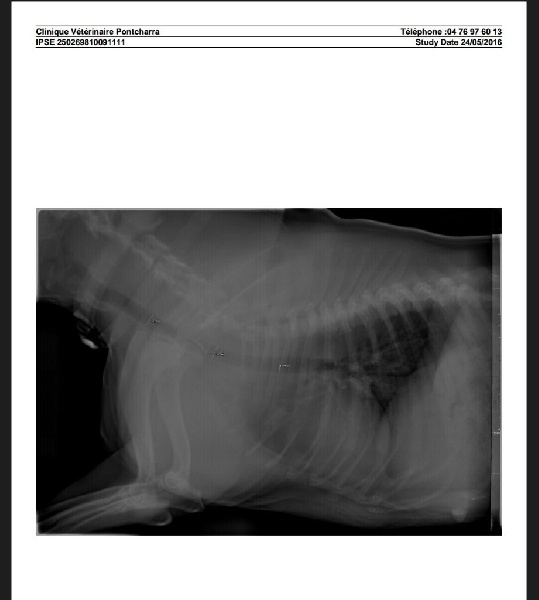

Radio de trachée. Largeur de 11 au 14 mm